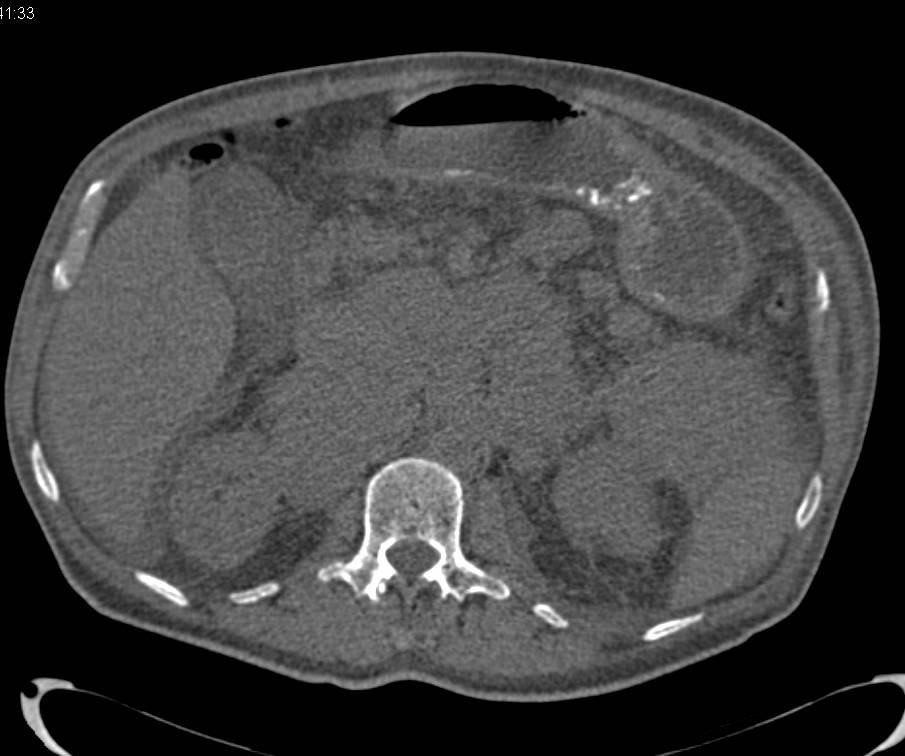

Recurrent Renal Cell Carcinoma Metastatic to the Spine